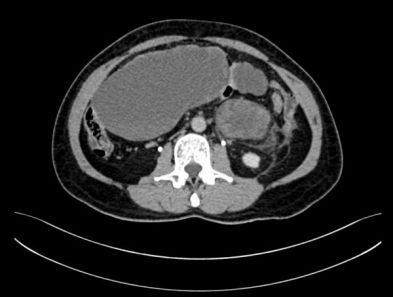

腹盆腔内见巨大混杂密度影,形态欠规则,最大截面约91×206mm,增强后病灶内实性成分可见强化,囊性成分未见强化。后腹膜未见明显肿大淋巴结,盆腔内见少许积液。提示:腹盆腔内巨大占位。

图1:CT图像表现